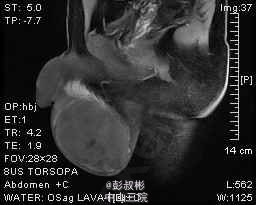

1、主诉:发现右侧睾丸肿大1年。 2、患者为青年男性,隐匿性起病。患者于一年前无明显诱因发现右侧睾丸变硬,并逐渐增大,无疼痛与牵引感,也不影响排尿和日常活动,未经任何诊治,近来自觉右侧睾丸钝痛,到我院门诊求诊,诊断为:"右侧睾丸肿瘤"。现为进一步诊治收入我科。起病以来,患者无寒战、发热,无恶心、呕吐、腹泻,食欲、精神、睡眠一般,大便正常,近期体重无明显下降。。 3、体格检查:双肾区无红肿、隆起,无叩痛,双侧肋脊点、肋腰点无压痛。腹平软,双侧输尿管走行区无压痛,膀胱区无膨隆,压痛阴性,双侧腹股沟区未触及肿物,阴毛呈男性分布,外生殖器发育正常,尿道外口未见异常,右侧阴囊内可触及右侧睾丸明显增大,约“20×10×8”cm大小,轻压痛,透光试验(-)。直肠指检:胸膝位,前列腺不大,质韧,中央沟存在,表面光滑,无结节,触痛阴性,指套未见沾血。 4、辅助检查:B超示:右侧睾丸肿瘤。盆腔MR平扫+增强扫描提示:右侧阴囊内占位,考虑睾丸来源恶性肿瘤,精原细胞瘤可能大。 5、诊疗措施:入院后予患者完善相关检查,三大常规及生化回报未见明显异常,未见明显手术禁忌症,考虑患者可耐受手术,拟予患者行右侧睾丸治疗根治性切除术。